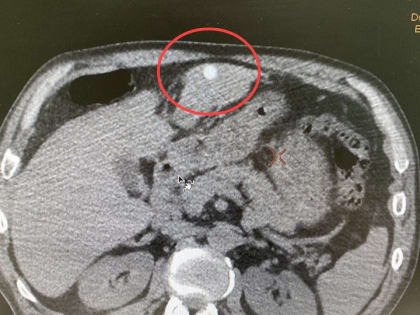

В Москве врачи спасли мужчину, теряющего вес из-за редкого заболевания

В инфекционную клиническую больницу (ИКБ) №2 бригадой скорой помощи был доставлен 35-летний житель столицы.